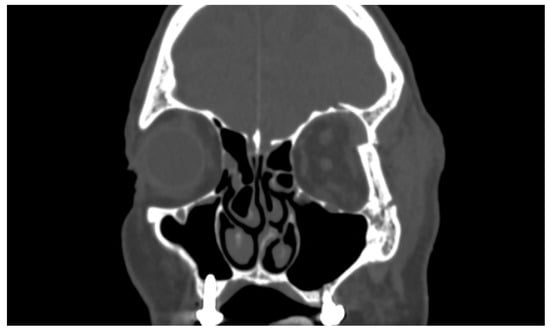

Incidence of Orbital Side Effects in Zygomaticomaxillary Complex and Isolated Orbital Walls Fractures: A Retrospective Study in South Italy and a Brief Review of the Literature

3. Results

- Zygomatic orbital fractures, the most frequent, in 60% (242 cases)

- Fractures of the orbital floor in 26% (104 cases)

- Fractures of the medial wall in 9% (38 cases)

- Fractures of the lateral wall in 3% (12 cases)

- Fractures of the orbital roof in 1% (6 cases)